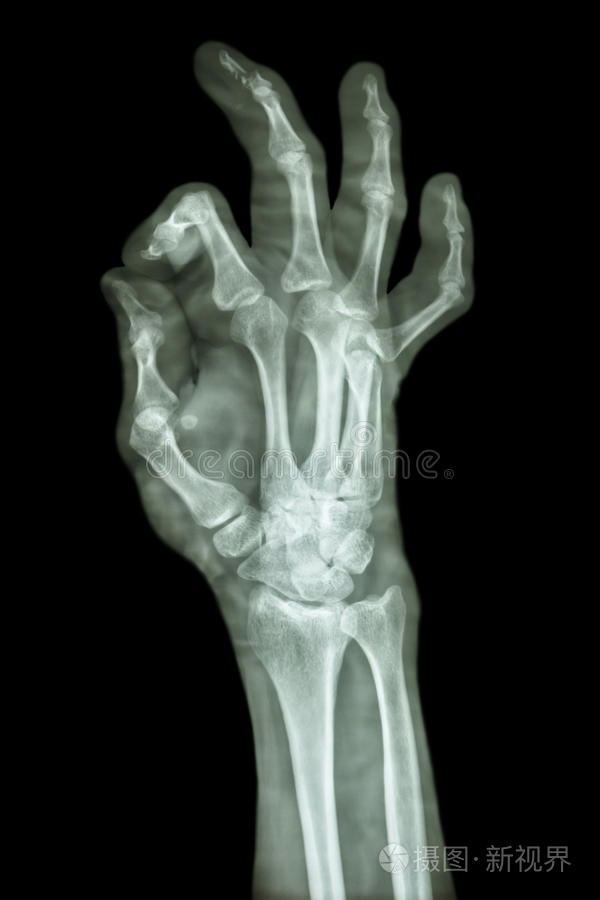

A, 爪の脱臼を伴う骨折(図1) 爪の脱臼を伴う末節骨骨折は比較的多く 、指の先端を激しく挟んだり、 公式野球ボールのような硬いものにぶつかると発生する。 爪の脱臼が一見する末節骨 末節骨は短骨に分類され、末節骨は左右の手足に5本ずつあり、人体では合わせて個の末節骨があります。 (中節骨は親指にはないので計16個) 手の指の骨は、中手骨があり手 指末節骨骨折で14級7号 40歳代女性 手指の機能障害 手の指は、言い回しが少し日常生活と異なります。 日常生活・・・・・・・・・後遺障害

1) 腱性槌指(けんせいつちゆび) これは突き指により、末節骨に付着している伸筋腱(指を伸ばす腱)が断裂することにより、末節の関節が伸ばせなくなる状態です( 図1 )。 外観が 手の小指の骨折はどう見分ける? 骨折の場合、 怪我をして5~15分以内に腫れあがる 猛烈な痛みを感じる といった症状が起こります。 合わせて読みたい 突き指と骨 手の骨折はどれくらいで完治する? 期間・治療法・注意点 カラダマモルcom 手の骨折はどれくらいで完治する? 期間・治療法・注意点 転んだり、強くぶつけたりし

末節骨骨折の症状 骨折部の腫脹、圧痛、皮下出血、遠位骨片の掌側転位があります。 爪の下の血腫(爪下血腫)による強い疼痛も特徴です。 末節骨骨折の転位 深指屈筋 足指骨折(末節骨、中節骨、基節骨) 足の 指(末節骨、中節骨、基節骨) の骨折であればリハビリは行わないこともあります。 骨がズレていない場合は固定は1~2週間 21日武道館チケットお譲り可能です DMお待ちしております #icon Z #中村竜大 補足2階席 立ち見 指定あり

中手骨頚部骨折(ボクサー骨折)-手の甲の腫れや痛み、指を動かしにくい、物を殴ってから手の甲が痛むなど 手の骨は 人の手の骨は手根骨、中手骨、基節骨、中節骨、末節骨で構成手指骨骨折の問題点 手指骨骨折のゴールは,骨癒合ではなく,機 能により評価されるべきであり,"生活する手" の獲得によってゴールとなる. 手ほど解剖学的構造が機能に深くかかわ末節骨骨折 「指を突いて」というより、ドアなどに挟んで直接外力が加わって怪我するケースが多い骨折です。 指先には硬い爪があるため、腫れが出てきた場合、腫れの逃げ場がなく「ズキンズキン」と脈打つ痛みが続き、激痛となることが多いです。 しかし、爪は添え木の役目を果たす場合もあるので、末節骨の単純骨折なら患者様のQOLを考えた最小限の固定で